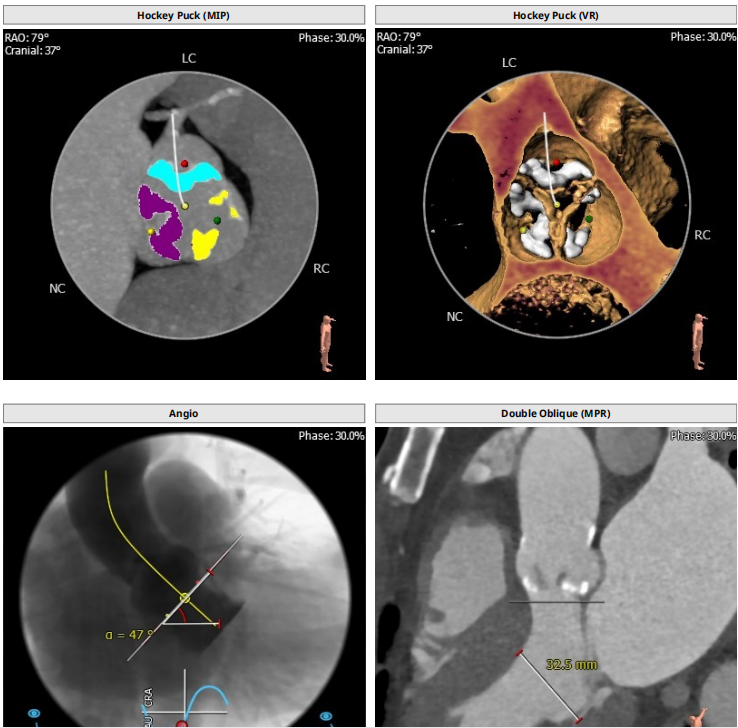

根部解剖:

VenusA26定位